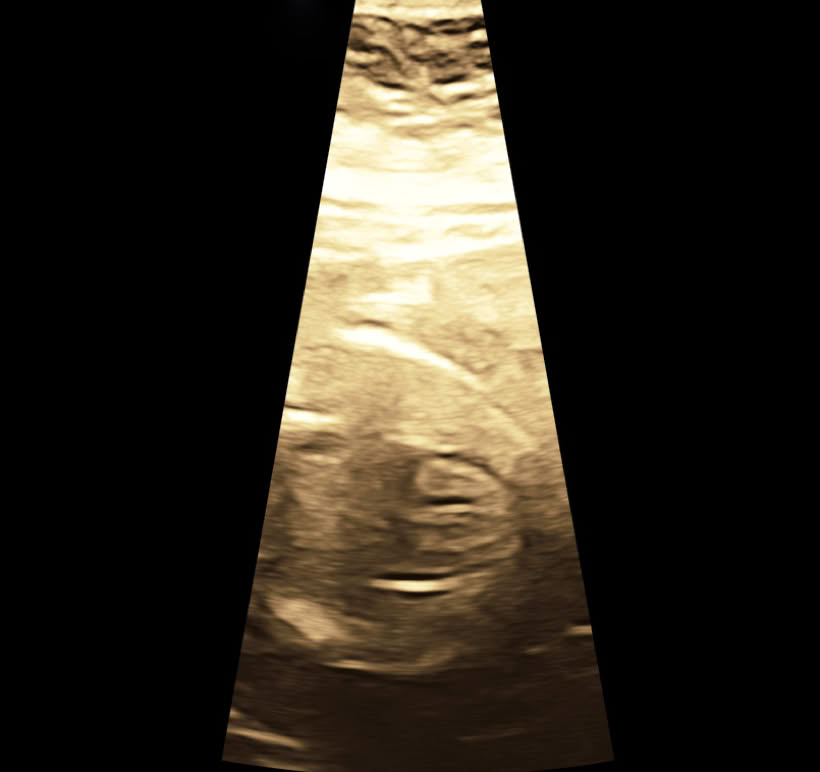

Herzdarstellung in der 22. SSW

‍Herz 23. SSW